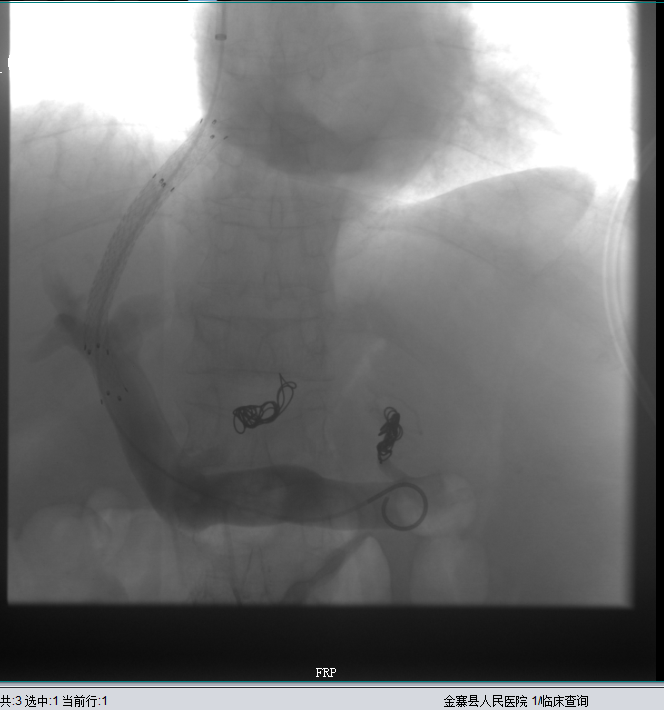

经肝静脉穿刺进入门静脉并显示门静脉